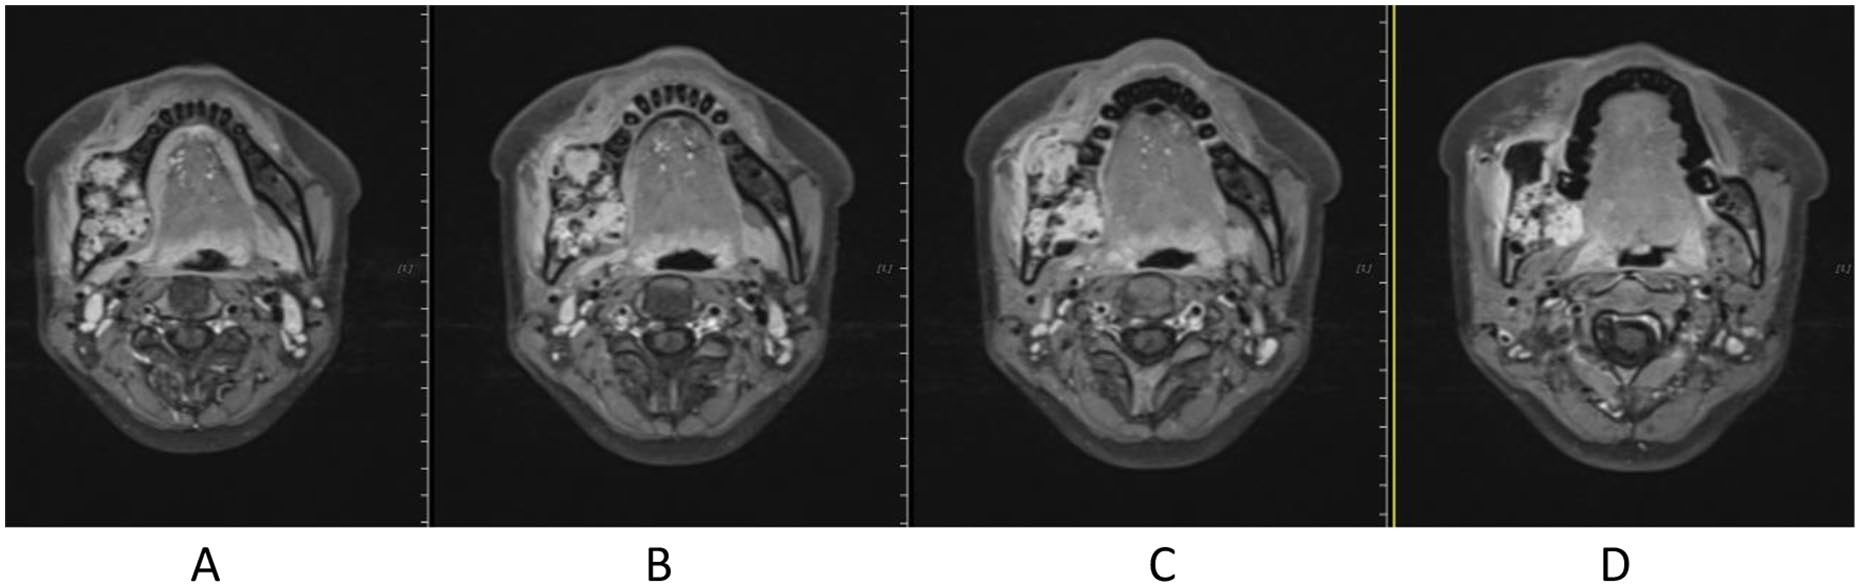

Treatment was tolerated well. During and after CIRT, there was only grade 2 skin (Figure 2) and oral mucosa acute adverse event, and no grade ⩾3 RTOG acute effect. During and after CIRT, her pain in the right mandible is continued but never aggravated, but painkiller is not needed; 6-month post completion of radiotherapy, she was in a very good clinical state, and the pain in the right mandible resolved completely. One to three months after CIRT, there were no significant changes of tumor size on MRI (Figures 3–6), just intensity of contract enhancement gradually diminished on contract-enhanced T1-weighted MRI; from 6months on, the size of the tumor decreased gradually (Figure 7); up to 16months after CIRT, it regressed to 3.6cm×3.2cm×1.7cm; and on 19months after CIRT, it regressed to 3.6cm×3.2cm×1.7cm, and the efficacy evaluation is PR (partial response) (Figures 8–10).

Figure 3. Before CIRT (2020-04) different slices of Contrast-enhanced MR T1: A. Contrast-enhanced MR T1, B. Contrast-enhanced MRI, TWI1, C. Contrast-enhanced MR T1, D. Contrast-enhanced MR T1